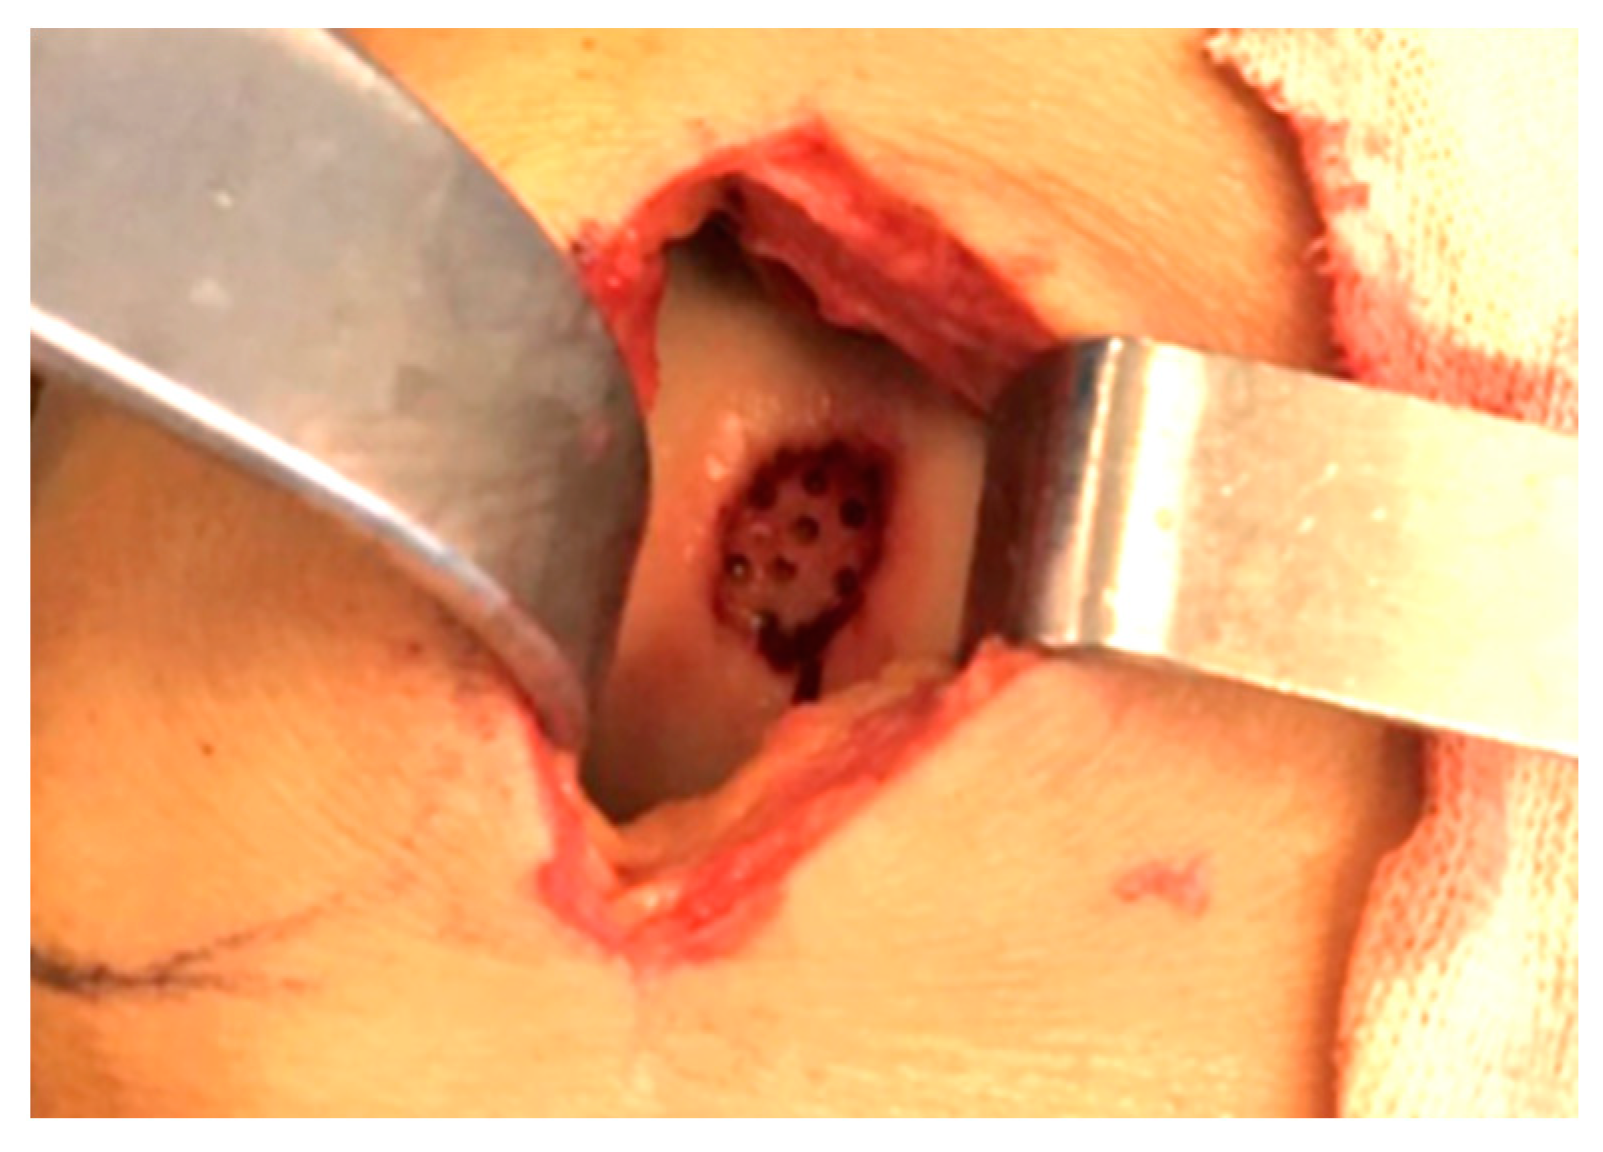

2.1. Surgical Procedure